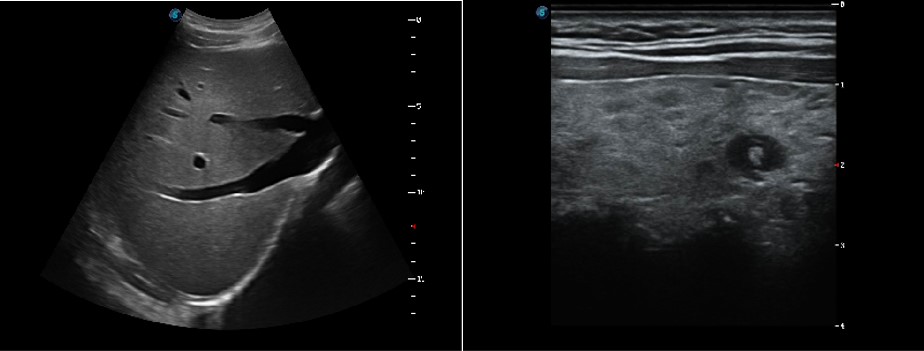

Hình ảnh được cải tiến, nâng cấp rõ nét hơn

SonoScape không ngừng tiến bộ xử lý việc cải thiện chất lượng hình ảnh của các sản phẩm siêu âm của mình để nâng cao sự tự tin, độ chính xác trong chẩn đoán cho các bác sĩ. Với những hình ảnh đặc biệt do P20 cung cấp, các cấu trúc giải phẫu rõ ràng hơn bao giờ hết.

Sonoscape P20 cung cấp hình ảnh vượt trội